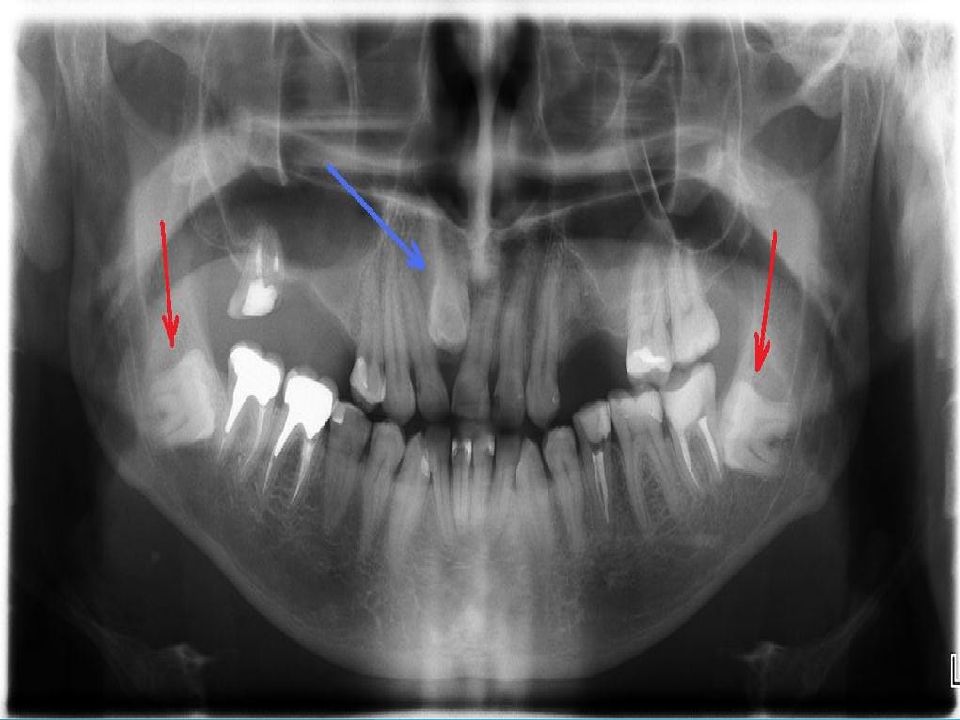

• Конусно-лучевая компьютерная томография — полуретенция зубов 1.8, 2.8, 3.8, 4.8, дистопия зубов 2.8, 4.8

Слайд 24: Конусно-лучевая компьютерная томография — полуретенция зубов 1.8, 2.8, 3.8, 4.8, дистопия зубов 2.8, 4.8